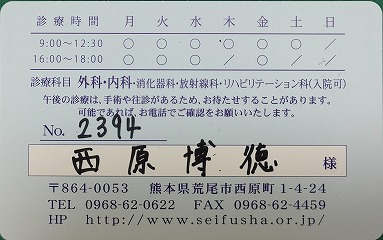

西原クリニック

2021.11.13より 西原クリニック 0968-62-0622